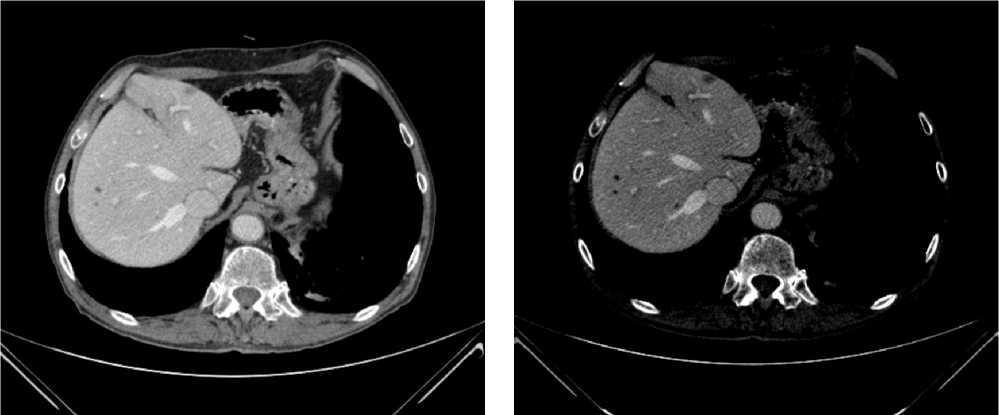

В результате обследования был установлен диагноз рака антрального отдела желудка (c)T4аN3вM1. По решению онкологического консилиума, учитывающего молекулярно-генетический профиль опухоли, а также возраст пациента, выраженность сопутствующей патологии (в анамнезе острое нарушение мозгового кровообращения (ОНМК), острый инфаркт миокарда (ОИМ), фибрилляция предсердий (ФП), постоянная форма), ограничивающей проведение ПХТ, была начата ИТ 1 линии пембролизумабом. С сентября 2019 г. по декабрь 2021 г. проведено 29 циклов ИТ 1 линии по схеме пембролизумаб в монорежиме с максимальным эффектом частичный регресс (рис. 4). Осложнений лечения не зарегистрировано.

Рис. 4. Частичный регресс по данным компьютерной томографии органов брюшной полости на фоне иммунотерапии пембролизумабом у пациента 81 года с диагнозом метастатический рак желудка с признаками микросателлитной нестабильности (декабрь 2021 г.; выживаемость без прогрессирования составила 25+ мес.)

Fig. 4. Partial response according to abdominal CT scan during immunotherapy with pembrolizumab in an 81-year-old patient diagnosed with MSI-H metastatic gastric cancer (December 2021; progression-free survival was 25+ months)

Для оценки метаболической активности остаточной опухолевой ткани выполнено позитронно-эмиссионная томография, совмещенная с компьютерной томографией (ПЭТ-КТ) в марте 2022 г., по результатам которого выявлено умеренное повышение уровня метаболической активности в проекции выходного отдела желудка и двух ЛУ брюшной полости, без значимой динамики в сравнении с предшествующим исследованием.

Для морфологической оценки патоморфологического регресса выполнена эзофагогастродуоденоскопия — эндоскопические признаки полного регресса опухоли. По результатам гистологического исследования, опухолевых клеток не выявлено.

Пациент находится под динамическим наблюдением без признаков прогрессирования процесса по настоящее время (выживаемость без прогрессирования составила 25+ мес.).